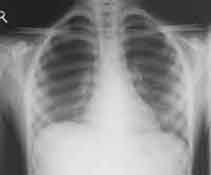

A chest radiograph was performed.

Enlarge the X-ray on your LEFT, enlarge the X-rray on your RIGHT

WHAT IS YOUR INTERPRETATION?